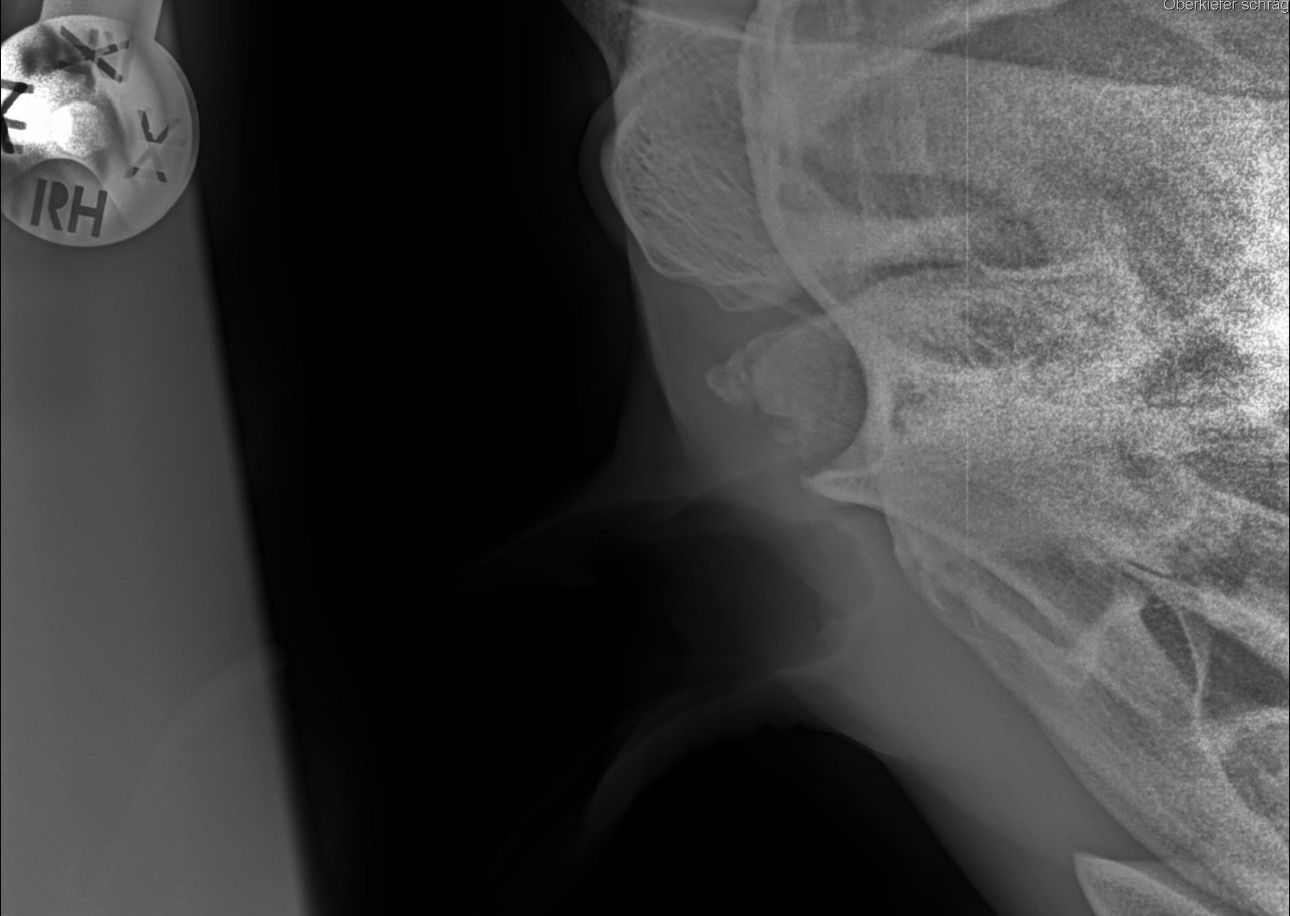

Weiterführende Untersuchungen: Röntgen

- makroskopische Umfangsvermehrung am linken Kiefergelenk

- röntgenologische Untersuchung beider Kiefergelenke zum Seitenvergleich

- beidseitige Befunde

Diagnose: beidseitige Kiefergelenksarthrose